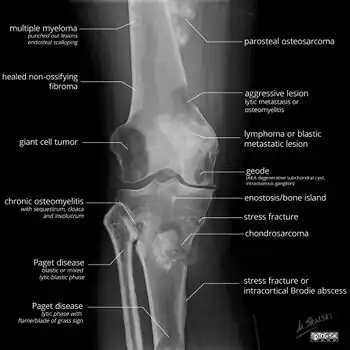

X-ray appearances of different types of bone tumors in > 30 years.